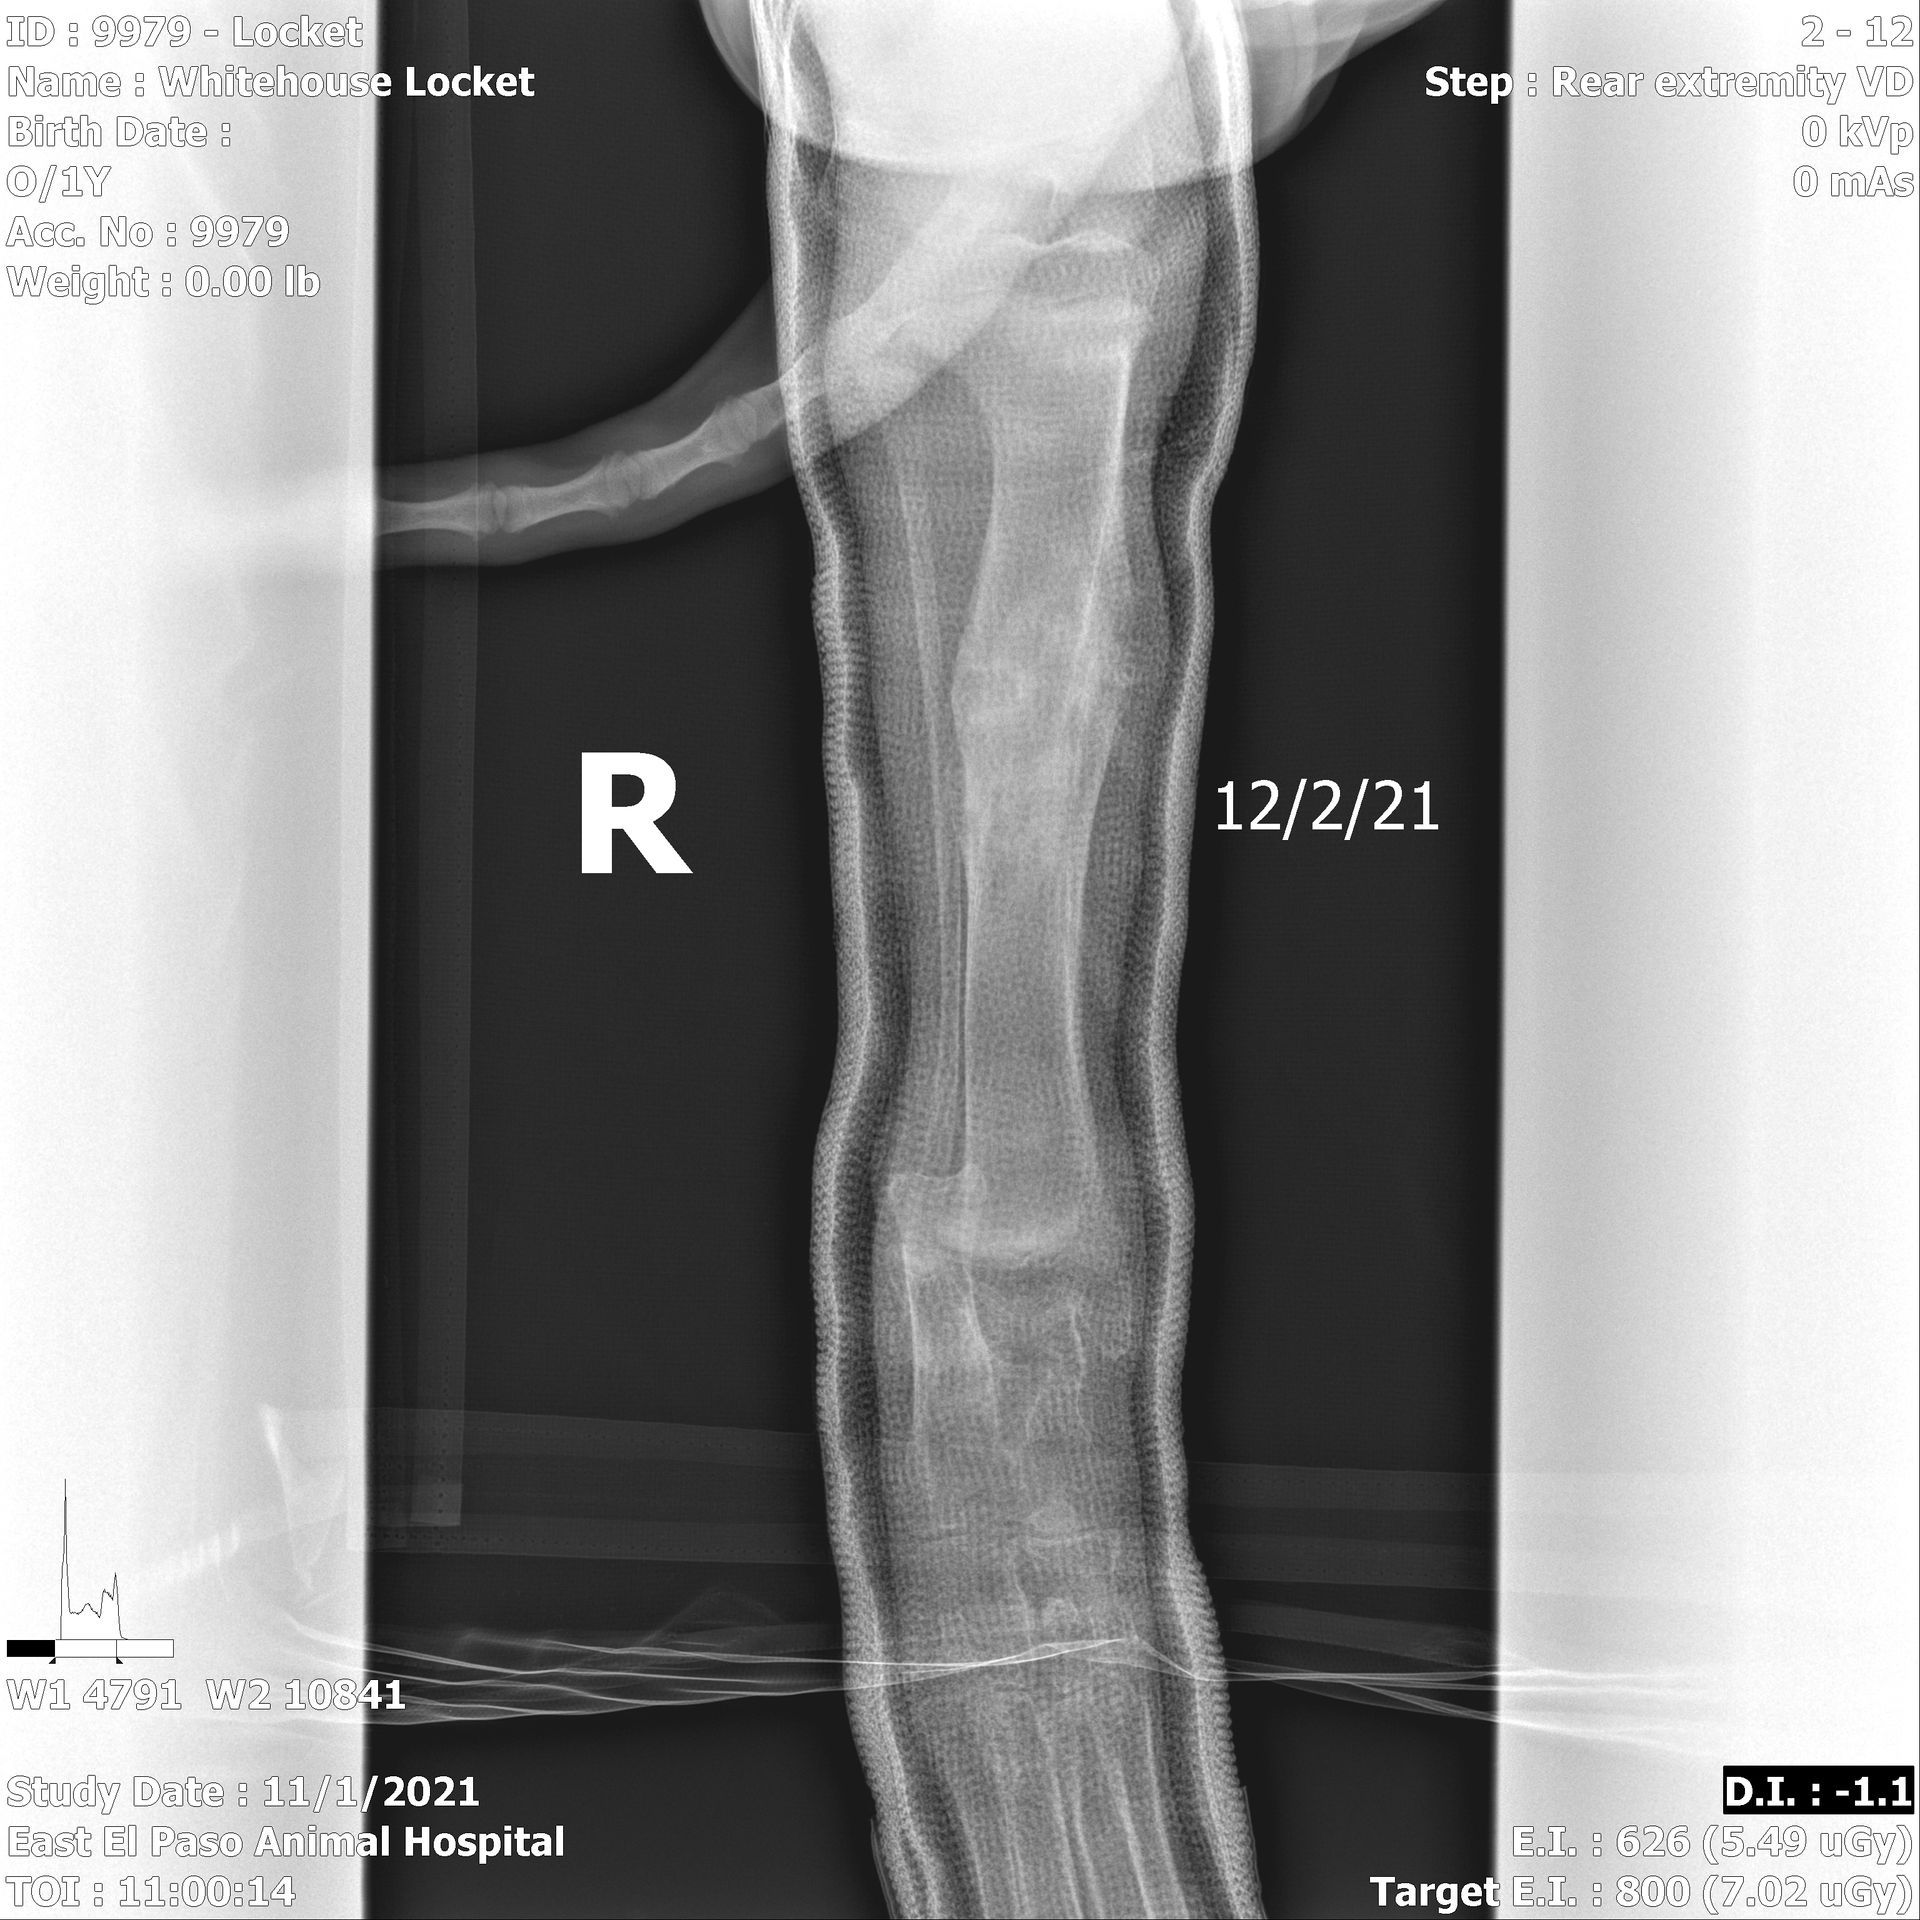

TRANSPARENCY is important! Our beloved Locket unfortunately broke her Right rear leg at 11 weeks of age on 11/1/2021. She was in a cast to her hip for over 6 weeks, on restricted activity several weeks more, and went through months of physical therapy. She recovered well enough to earn her Championship (winning both of her specialty majors on movement) and has continued to participate in lots of fun activities. Unfortunately, as is often the case with injuries like this, her hip joint was affected and there have been changes to the femoral head over time. OFA classified her as Mild UR (Mild Unilateral Right). We knew this was likely and we submitted her X Rays to OFA anyway (and checked the box!!)- both in the interest of transparency & education. For that reason we will also share photos & X Rays below.